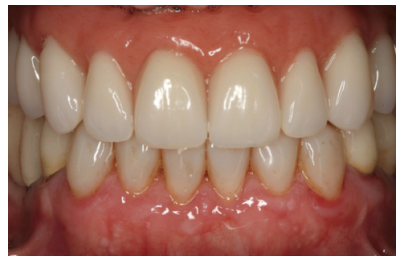

Cuatro meses después se procede a la carga de los implantes insertados en esta segunda fase quirúrgica. De nuevo se opta por unas segundas prótesis provisionales de carga progresiva, elaboradas del mismo modo que las anteriores Tres meses después la oclusión está preparada para la confección de la prótesis definitiva, por lo que se transforma la prótesis en una prótesis metal-cerámica, atornillada sobre transepitelial confeccionada mediante cad-cam (Figuras 25-26). La paciente ha recuperado la función demandada, así como la corrección de la oclusión de la prótesis completa, que presentaba una mordida cruzada lateral derecha con disminución de la dimensión vertical al inicio del tratamiento. La paciente acude a sus revisiones y el tratamiento se mantiene estable tal como se muestra en las imágenes tomadas a los 10 años de seguimiento (Figuras 27-28).